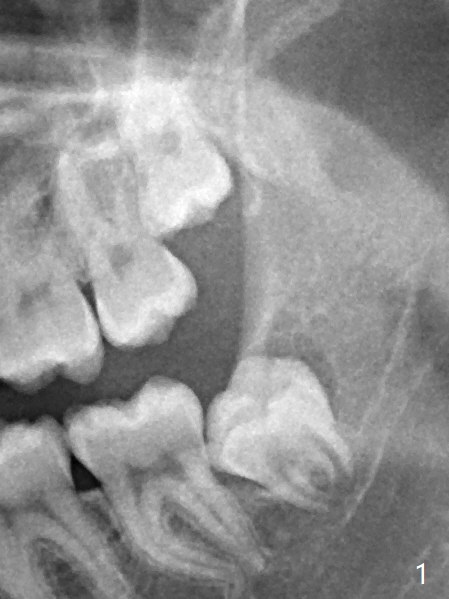

Two years 10 months between Fig.1 and 2.  The chief complaint is mastication pain of the upper 3rd molars, as related to the thin gingiva upon incision.  Overlapping and crowding are much more severe as seen intraop than X-ray indicates.